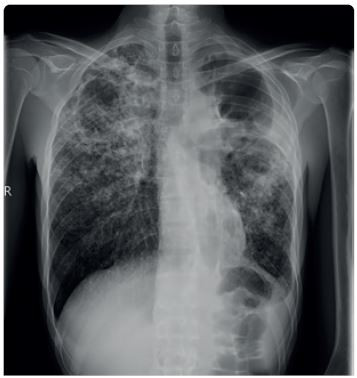

Diagnóza tuberkulózy se opírá o anamnézu, klinické symptomy, patologický radiologický nález a zásadní význam má bakteriologický průkaz patogenu ve vyšetřovaném materiálu. Radiologický nález u TB bývá charakteristický, ale nikoli specifický (obr. 2). Radiologicky může tuberkulóza imitovat jakékoliv plicní onemocnění. Nicméně zadopřední skiagram hrudníku doplněný o boční projekci je základním vyšetřením u plicní i mimoplicní TB. Pokud u pacienta s patologickým radiologickým nálezem není ve sputu M. tuberculosis jednoznačně prokázáno, doplníme k upřesnění nálezu vyšetření výpočetní tomografií (CT) s vysokým rozlišením (HRCT hrudníku). V případě podezření na mimoplicní TB indikujeme zobrazení ostatních tkání a orgánů – magnetickou rezonanci (MR) centrálního nervového systému (CNS), skiagramy či CT, ev. MR kostí, vylučovací urografii, CT břicha apod. (obr. 3).